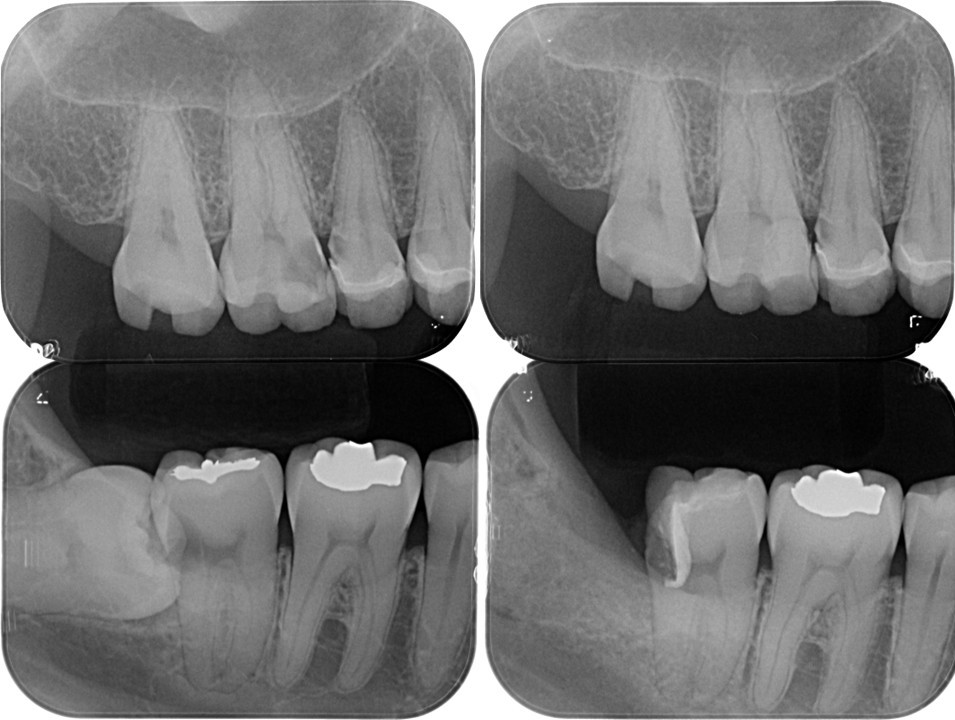

臨床例「直接覆髄法」を用いた一症例(図6)

術前レントゲン

髄角付近までう蝕が進行していることが確認できる

(図12)術直後のレントゲン像

近心髄角に一部MTAと思われる不透過像を認める

術後7年以上経過して状態は安定している(図13)。

術後7年との比較 左:2017.11.09 右:2024.11.23

近心髄角付近にはデンチィンブリッジ形成による象牙質様の不透過像の生成が確認できる